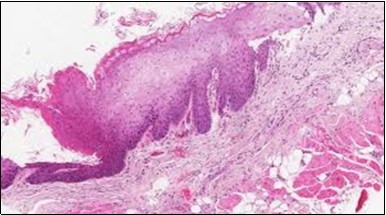

Figure 11.HCL Oral mucosa with soft tissue infiltration of hairy cells(27).

Figure 12.HCL: hairy cells with broad and fine projections of the cytoplasm(28).